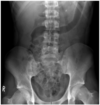

What are the main sites the ulcerative colitis occurs?